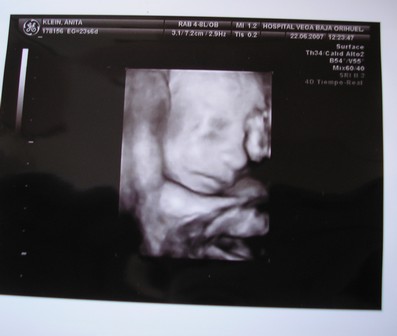

A kisbabád meg nagyon szép, nagyon jó kép lett róla. Olyan jó, hogy kislány lesz, nagyon sok szép kisasszonynév van, bő a választék. Bezzeg fiúból... ezért nincs is még lekonkretizálva mindig a mienké, de nem lesz nevesincs királyfi, az tuti